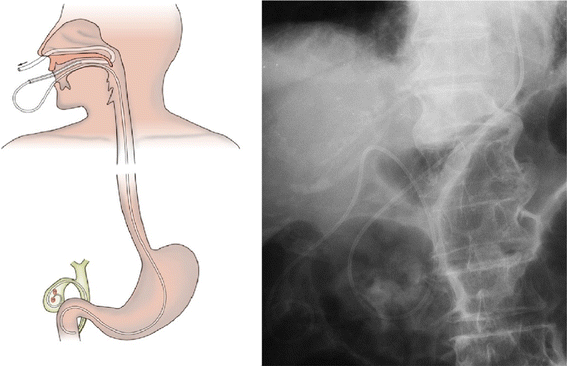

ENGBD involves placement of a naso-gallbladder drainage tube and generally does not require biliary sphincterotomy. After successful bile duct cannulation, a 0.035-in. guidewire is advanced into the cystic duct and subsequently into the gallbladder. At times, a hydrophilic guidewire is useful for seeking the cystic duct. Finally, a 5–8.5 Fr pigtail naso-gallbladder drainage tube catheter is placed into the gallbladder (Fig. 3).

Fig. 3

Endoscopic nasobiliary gallbladder drainage (ENGBD) procedure. Left Schema of ENGBD. Right X-ray shows nasobiliary catheter placed in the gallbladder